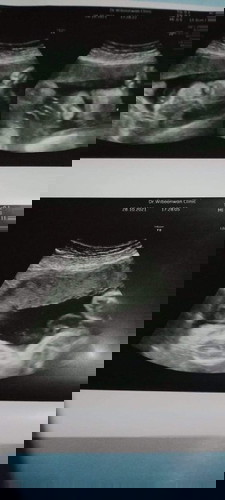

ฟังผลตรวจเลือดเมื่อวันที่ 21 มิถุนายน ผลคือธาลัสซีเมียแฝงทั้งพ่อและแม่ ทางโรงพยาบาลได้ส่งเลือดไปตรวจที่โรงพยาบาลอีกแห่ง ว่าเป็นธาลัสซีเมียชนิดไหน รอฟังผลอีกรอบ วันที่ 12 กรกฎาคม กลุ้มใจ กังวลและ จิตตกมากค่ะ ใครมีประสบการณ์แบบนี้บ้างคะ (กลัวต้องยุติการตั้งครรภ์มากค่ะ ท้องแรก) #ขอบคุณล่วงหน้านะคะ